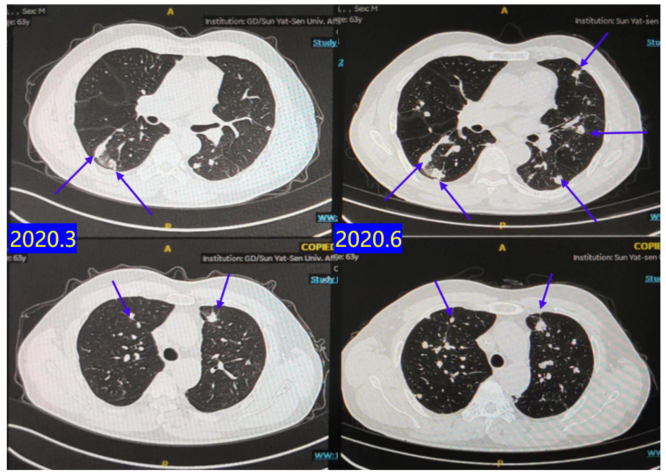

2020.03-2020.06:行贝伐珠单抗 + FOLFOX治疗4周期。

疗效评估:C4评估为PD(图5)。PFS 3个月。

2020.06-2020.12:行呋喹替尼靶向治疗。

疗效评估:C2评估SD,C4评估PD(图6)。PFS 6个月。